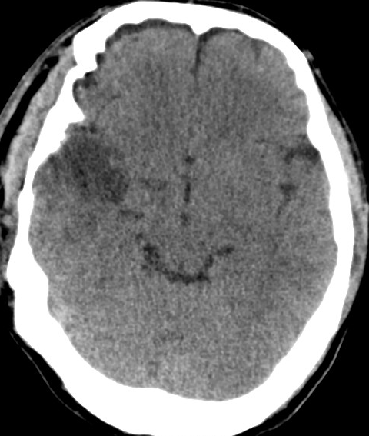

2014-9-29 CT

2014-10-5 CT